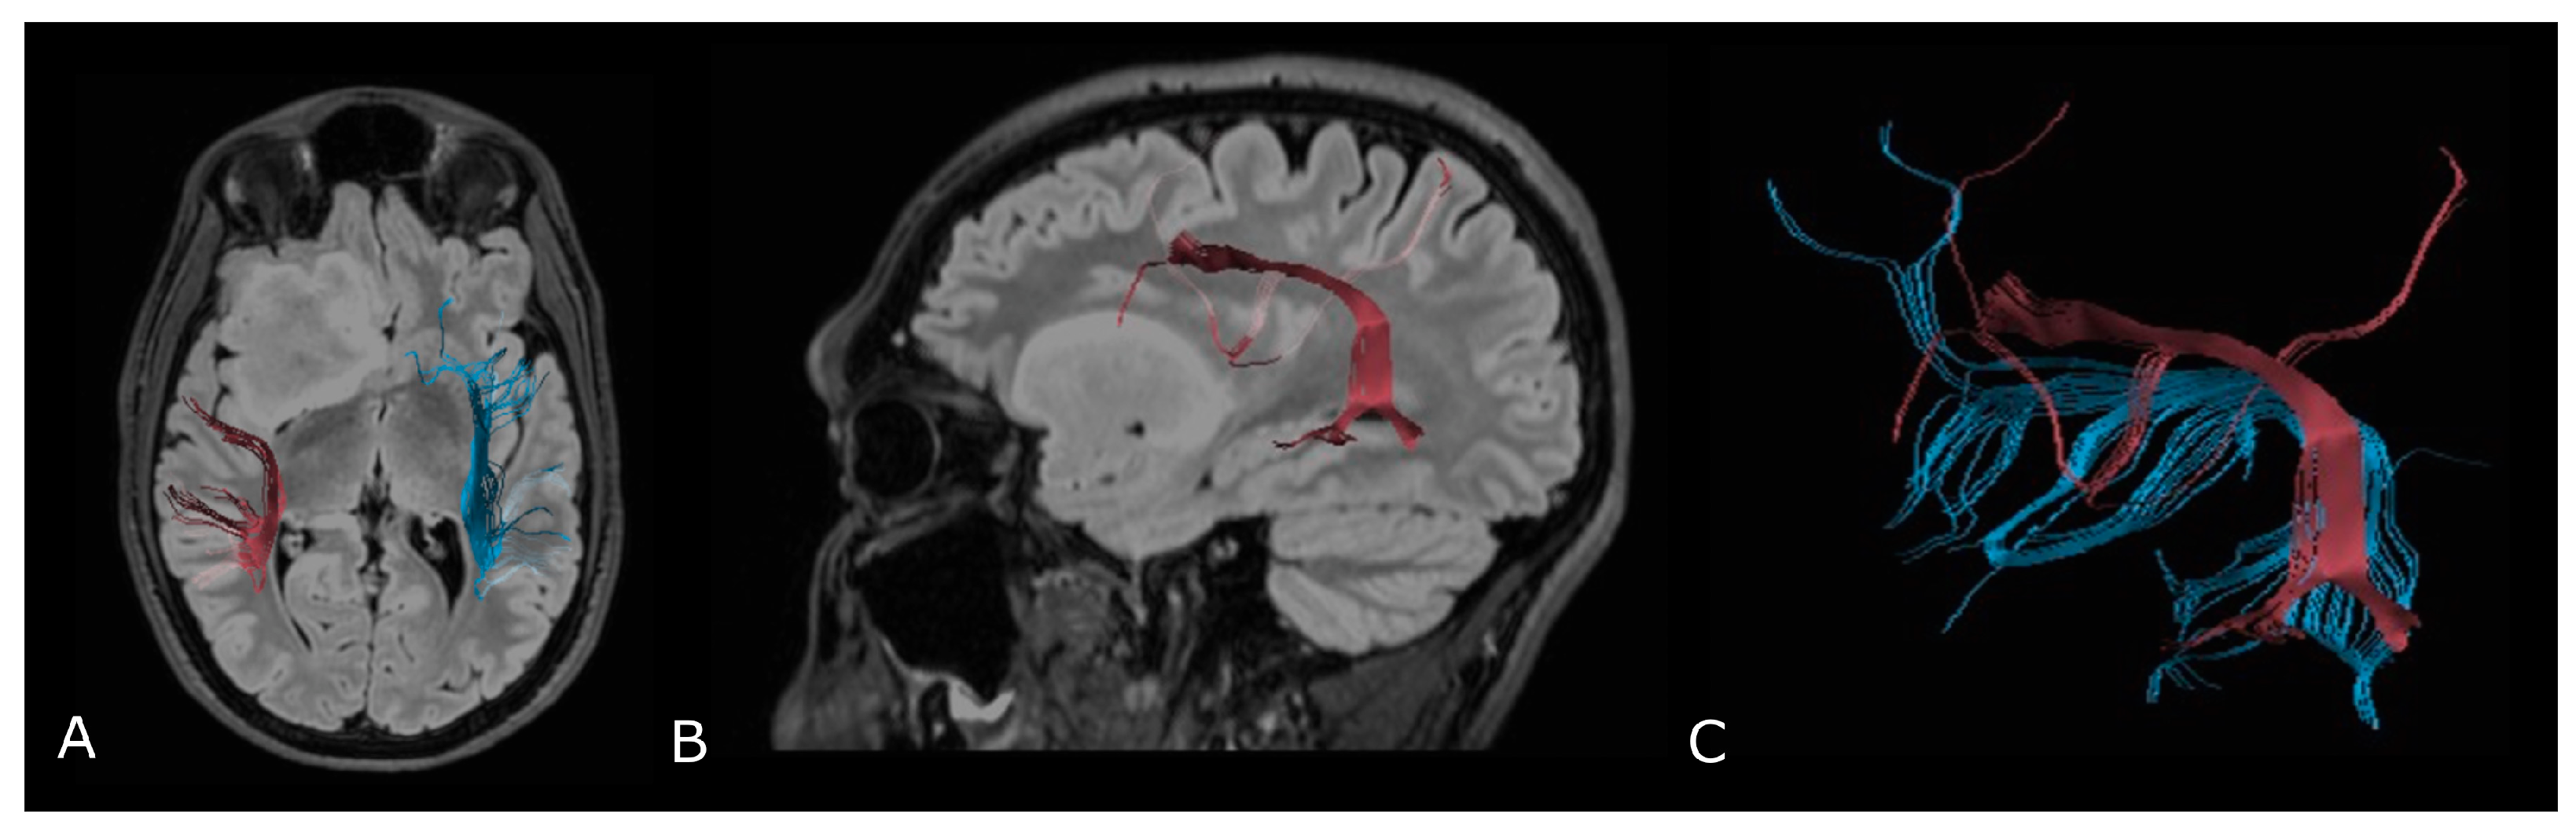

4.2. Diffusion Tensor Imaging: Technical Notes and Clinical Application

4.2.1. Tumor Grading and Extension

4.2.2. Presurgical/Intraoperative Assessment

4.2.3. Radiotherapy/Radiosurgery Planning

4.2.4. Differentiation between Recurrent Tumor and Radiation Injury